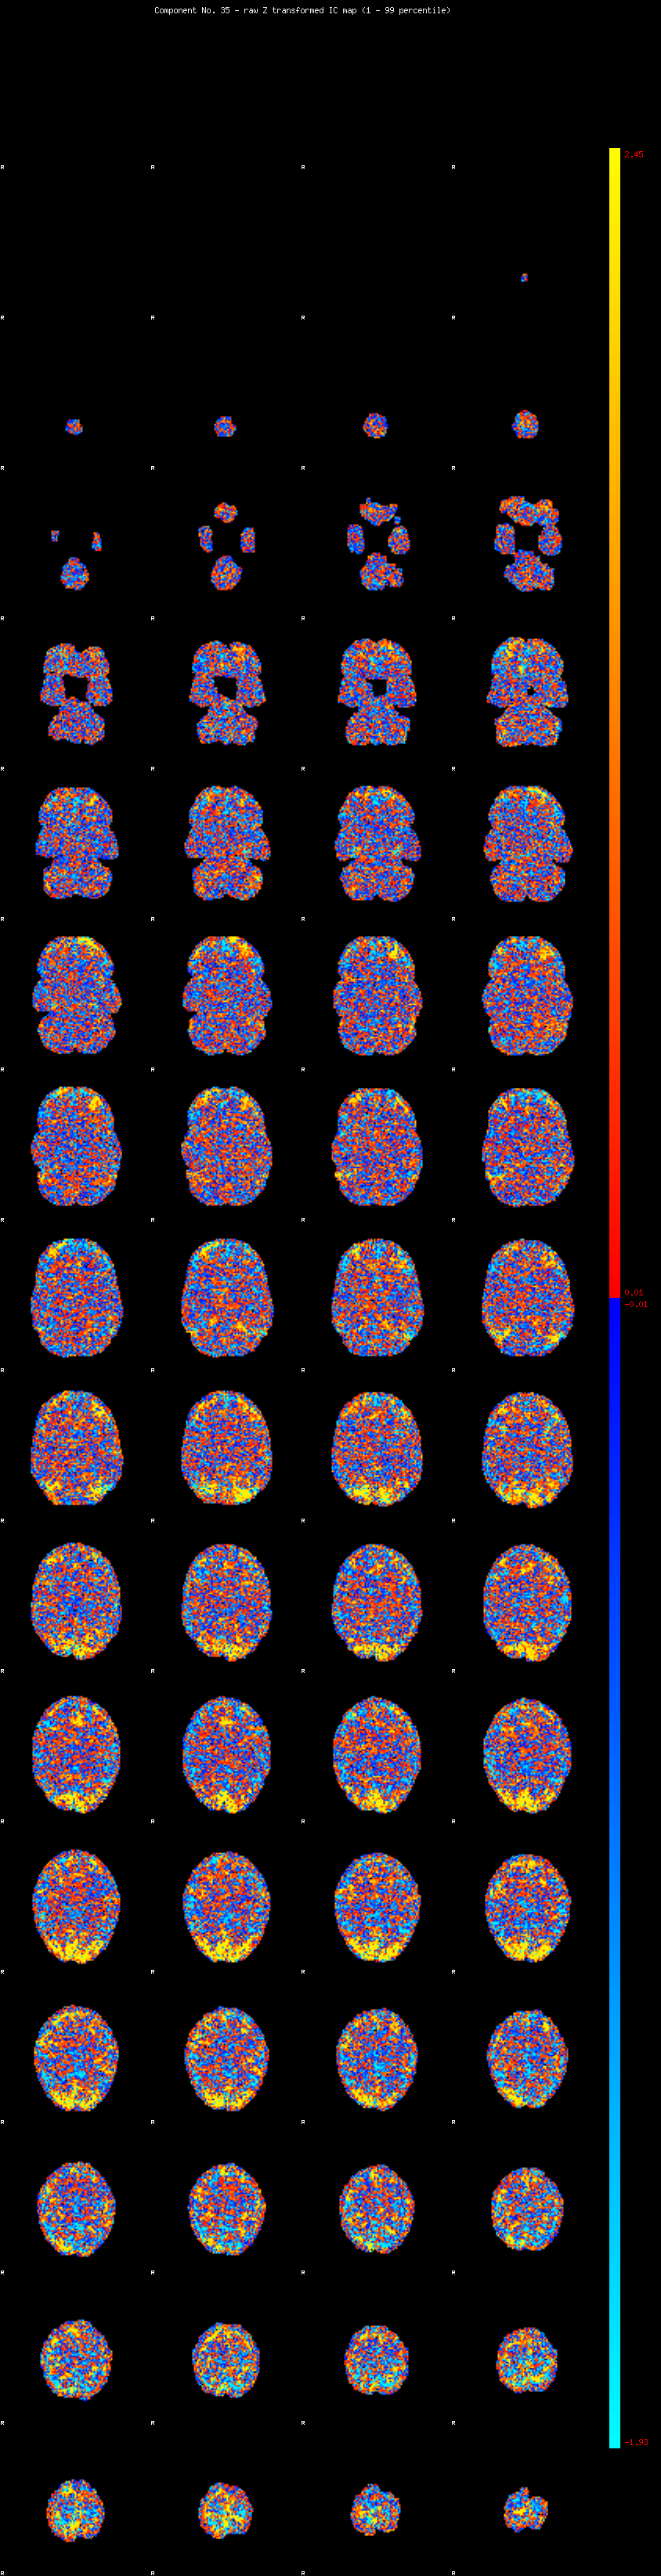

IC_35 Mixture Model fit

Means : -0.000000 3.802411 -2.670707

Vars : 1.000000 6.685658 1.459577

Prop. : 0.926124 0.050746 0.023130